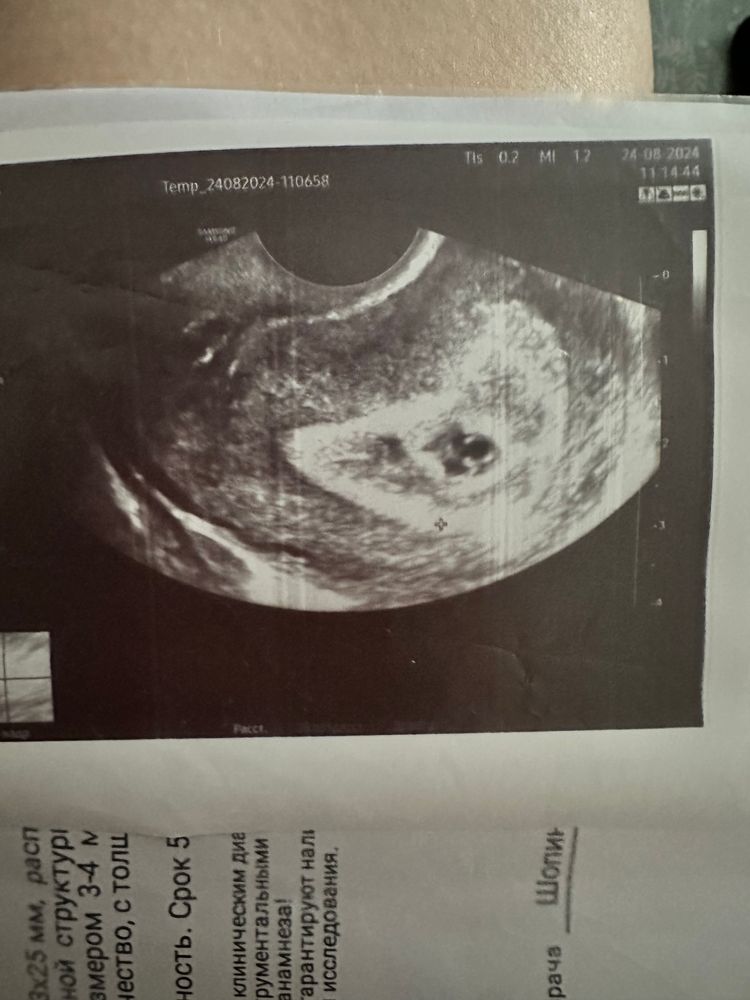

Врач поставил срок беременности 5,5

Говорить что возможно видит эмбрион чик, но пока не точно

кто нибудь видит эмбрион?😬

Я еще слабо умею что-то разглядывать на узи, но мне кажется, что вижу! Мне сегодня такого же показывали на узи, и сердцебиение

Кольцо с бриллиантом точно видно - эмбрион и мешочек желточный.